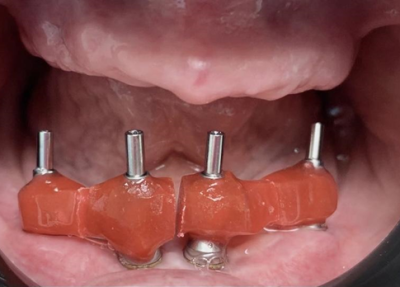

Фото до и после процедуры:

All-on-4 на нижней челюсти.

Полный съёмный протез на верхней челюсти (Акри фри).